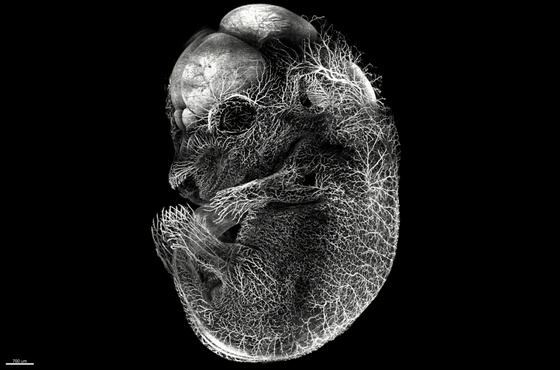

作品名称:生命之光

作者姓名:黄海涛

作者单位:厦门大学

科学意义/图片创意: 神经发生是神经系统内增殖分化产生新神经元的重要过程,对于各组织内的神经连接建立至关重要。传统的组织学切片无法完整地观察到整个胚胎的神经投射,限制了我们对于胚胎神经发育的相关研究及展示。本图利用组织透明化技术对E11.5D小鼠进行全组织免疫标记及3D成像,可观察到小鼠胚胎完整的神经纤维投射(β-III tubulin白色),对于我们进行相关神经环路研究提供了极大的便利。